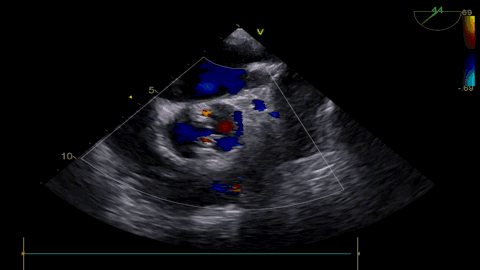

球扩后超声

发生瓣叶切割,无窦侧瓣叶切割,Type0结构形变为类三叶瓣结构。